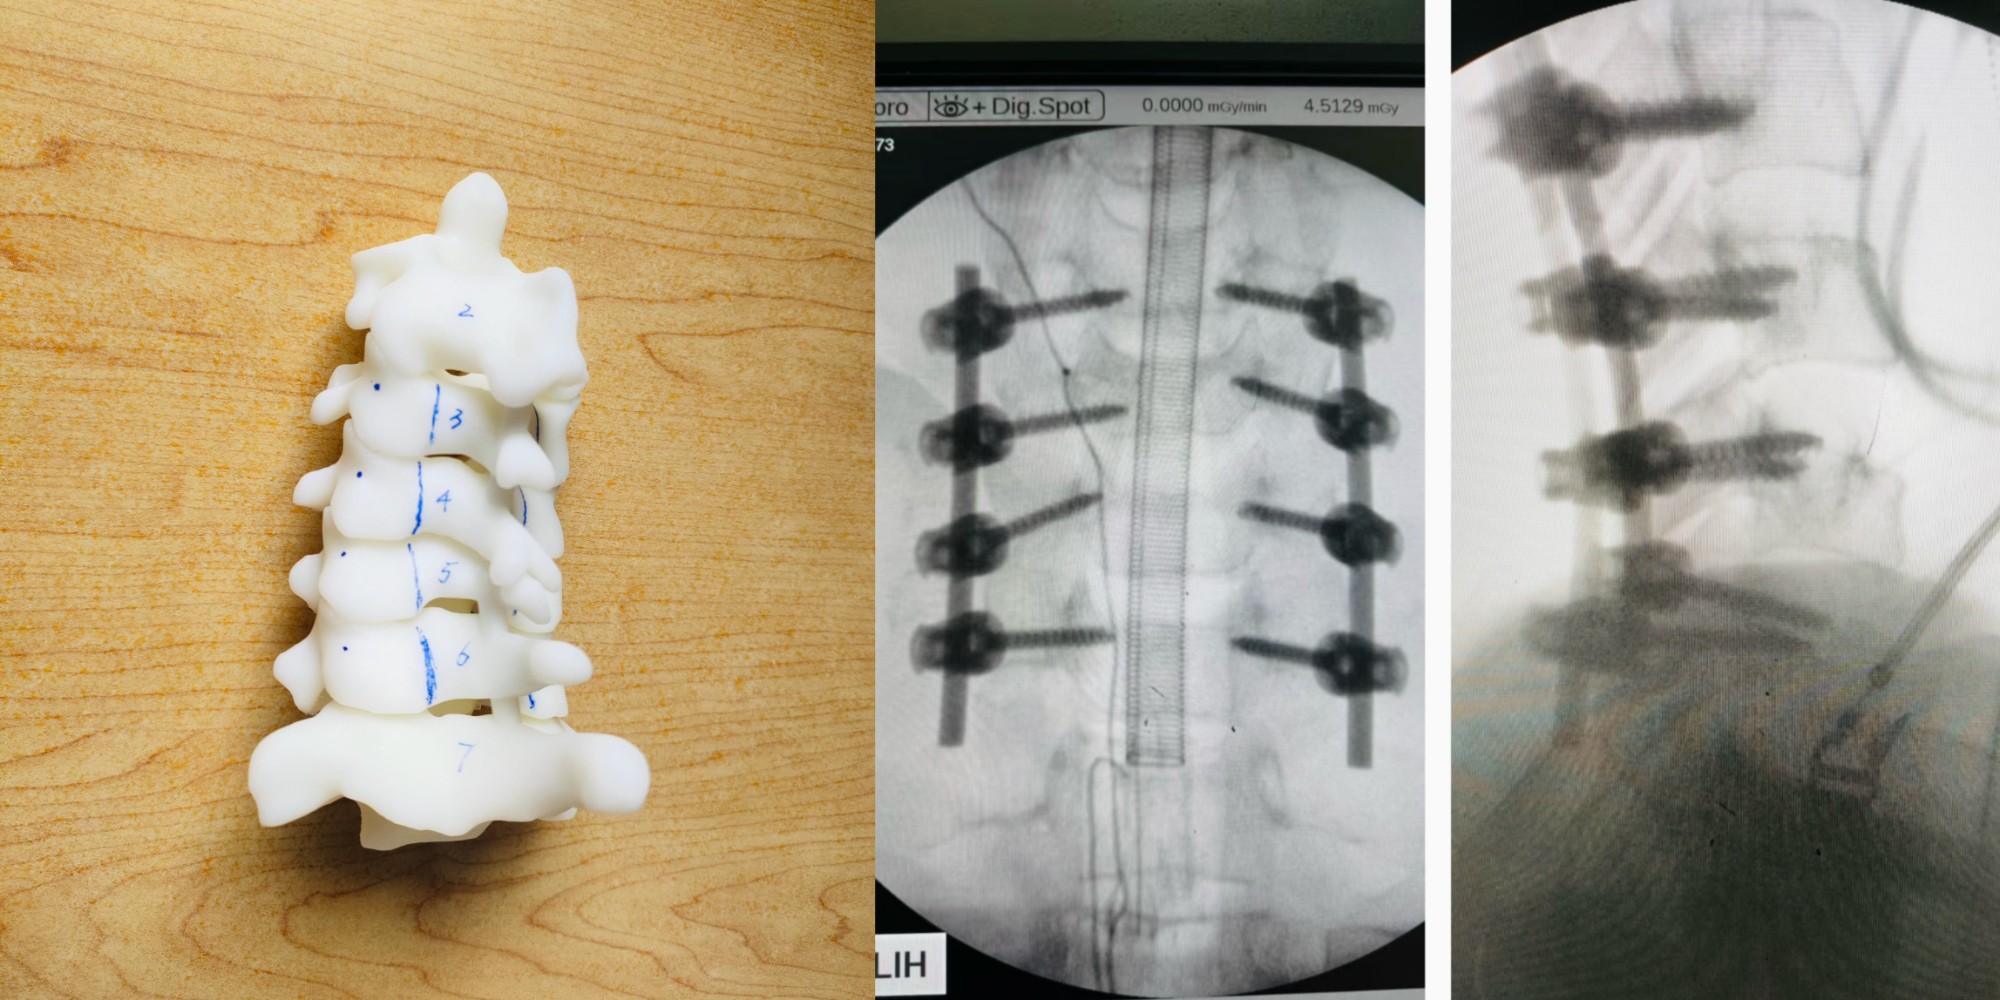

颈椎手术应用3D打印技术精准定位

脊柱骨折减压椎弓根螺钉内固定术